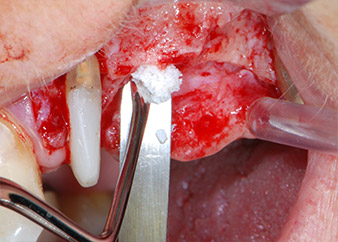

Avant la pose de l'implant, les tissus infectés ont été retirés de l'os alvéolaire sur le site de l'implant et autour des dents piliers à l'aide d'un insert initialement conçu pour le façonnage de l'os et la récupération des copeaux d'os (Piezomed, insert B5) (Figures 6 et 7).

Les lits implantaires ont été préparés sur les sites 25 et 26 à l'aide d'instruments rotatifs, utilisés dans un contre-angle avec un rapport de transmission 20:1 avec un nouveau moteur d'implantologie puissant (Implantmed, W&H) (Fig. 8).